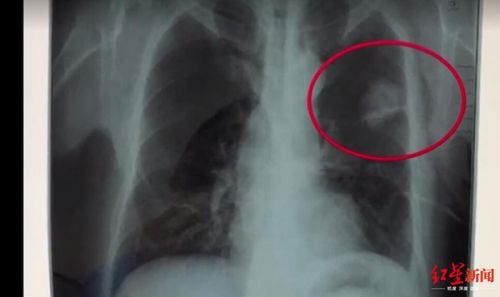

體檢胸片顯示的陰影

離職前,陳志鵬在四川攀枝花的一家健康檢查專業(yè)機構(gòu)體檢,體檢時醫(yī)生發(fā)現(xiàn)其肺部有陰影,認為是其自述的胸前佩戴的玉佩造成的,出具了心肺隔未見明顯異常的結(jié)論。

在最終出具體檢報告前,體檢醫(yī)生再次致電陳志鵬,要求其進行復查,但是他依然提出不用復查。在法庭上,檢查陳志鵬胸片的醫(yī)師出庭,法官對她進行了詢問,該女醫(yī)師稱,“就是他(陳志鵬)一直說戴了一個玉佩,正常說來玉佩在胸片上,會顯示有陰影的,不可能就消失了,然后再問他癥狀,他說什么癥狀都沒得,也不咳嗽,也不胸悶,他說正常的很,然后我們結(jié)合這些癥狀和胸片的情況,就出具了未見明顯異常的報告。”